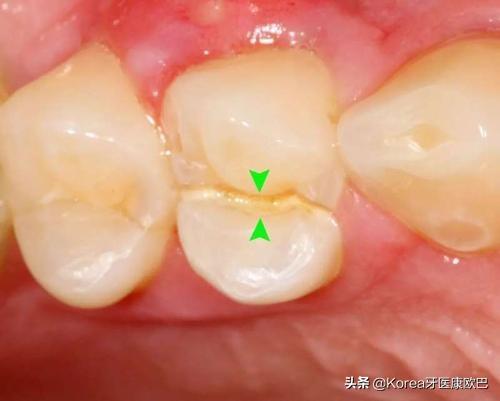

3.牙隐裂引起的疼痛

由于牙齿的使用不当,咬硬的东西等。有可能会发生牙隐裂(牙齿上有很小的裂缝,不容易发现)的情况,导致牙齿疼痛。自己很难发现,可以到医院让医生检查。